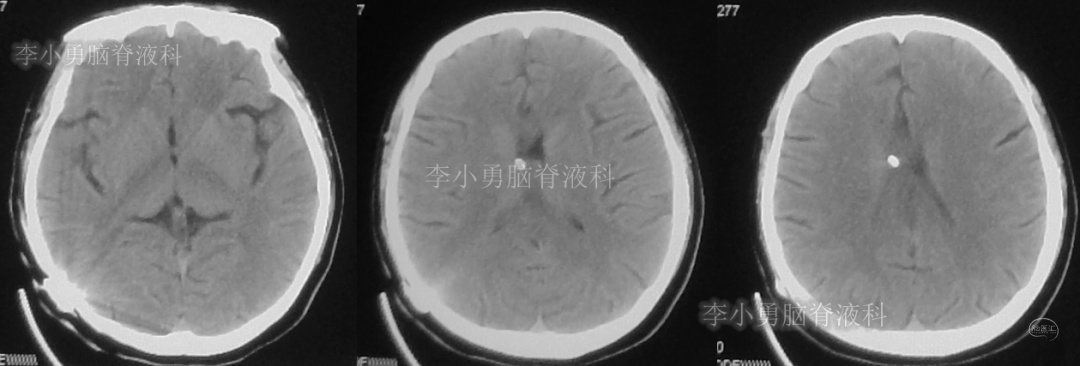

患者于2018年1月29日,突发头痛、头晕、恶心、呕吐,并高热40度。在当地医院门诊输入4天抗生素后发热缓解,但出现了双眼不能上视(眼球不能向上看)。5天后即2018年2月3日,在当地的第1家医院:浙江省海宁市某医院行头颅CT(图-1)发现脑室扩张,当地医院诊断为“梗阻性脑积水”。

图-1:2018年2月3日头颅CT